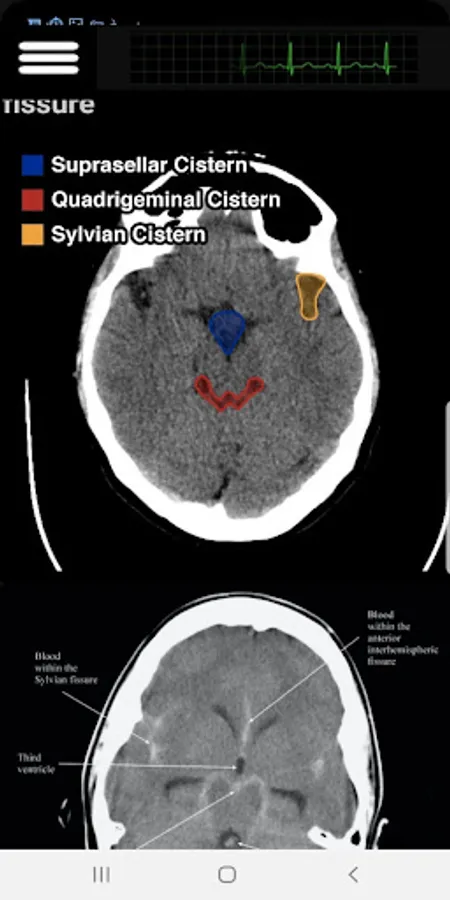

In this app, I covered the most important Head CT-Scan features that a practitioner face in his clinic or in an ER. Subjects like Hoe to read in an organize way, Blood, cisterns, Brain, Ventricles and bone.